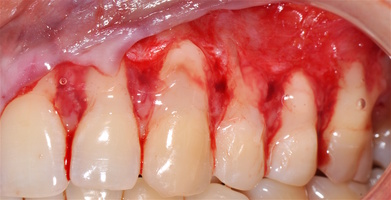

1. Генерализованные рецессии в области нижней челюсти оперировались в один этап все 12 зубов, фронтальный участок с аутотрансплантатом от 3.2 до 4.2 зубов. А дистальные участки от 3.6 до 3.3 и от 4.6 до 4.3 зубов с использованием пластического материала ТМО (dura mater) (рис. 4а-з).

4. Этапы хирургического лечения рецессий десны на нижней челюсти

3.2-4.2 зубы были прооперированы методом, сочетающим вестибулопластику с одновременным увеличением ширины и толщины прикрепленной десны при помощи свободного десневого аутотрансплантата (операция Bjorn, 1963 г.).

1. Подготовка принимающего ложа. Включает в себя формирование полнослойно-расщепленного слизисто-надкостничного лоскута (полнослойного в области зенитов рецессий, расщепленного билатерально области рецессии десны), рассечение и отслаивание слизисто-мышечных волокон вестибулярно ниже мукогингивальной границы, деэпителизация межзубных сосочков.

2. Обработка поверхностей корней зубов. Включает ультразвуковую обработку скейлером для очищения от минерализованных зубных отложений и мягкого зубного налета, экспозицию геля ЭДТА 17% в течение двух минут, механическое удаление слоя бесклеточного цемента импрегнированного микроорганизмами зоноспецифическими кюретами, полировку пародонтологическими борами («фасолька» и «обратный треугольник»).

3. Получение аутотрансплантата: начинается с определения толщины донорской зоны и замеров размера будущего трансплантата. Зона забора от второго премоляра до третьего моляра верхней челюсти. Глубина погружения брюшка скальпеля 2 мм, далее трансплантат оптимизируют — деэпителизируют по периметру.

4. Затем проводиться позиционирование аутотрансплантата в области рецессий и принимающего ложа двумя-тремя узловыми швами; после аутотрансплантат стабилизируют прижимающими двумя-четырьмя матрасными крестообразными швами, что позволит плотно прижать аутотрансплантат и избежать образования «мертвых» зон для питания аутотрансплантата.